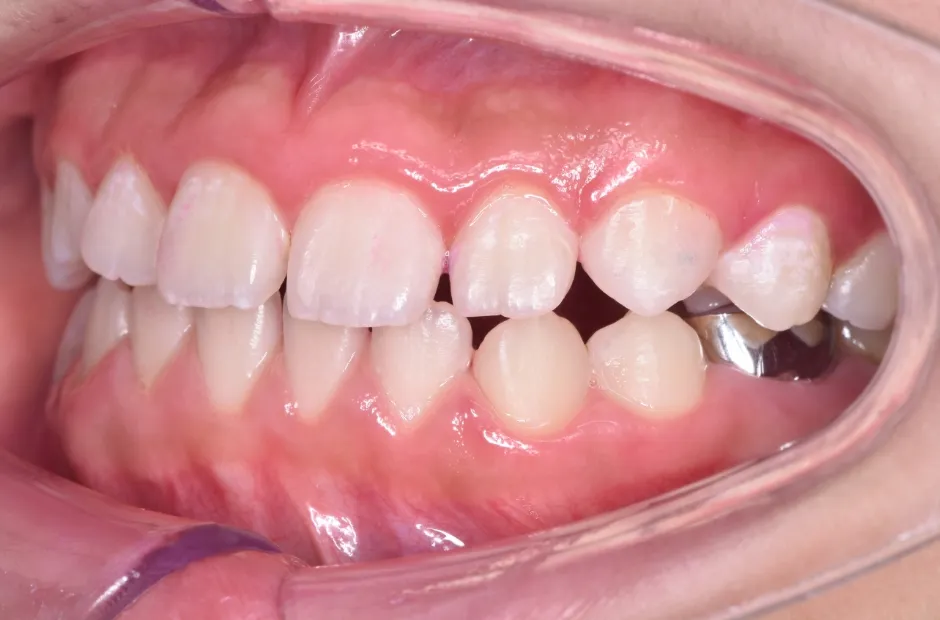

叢生

| 診断名・主訴 | 叢生 |

|---|---|

| 年齢・性別 | 10歳・女性 |

| 治療期間・回数 | 2年半 |

| 治療に用いた主な装置 | 拡大床装置 |

| 抜歯部位 | なし |

| 治療費 | 30万円(税抜) |

| リスク・副作用 | 装置による違和感・疼痛・歯肉退縮・歯根吸収・虫歯のリスクなど |

治療前

治療中

治療後